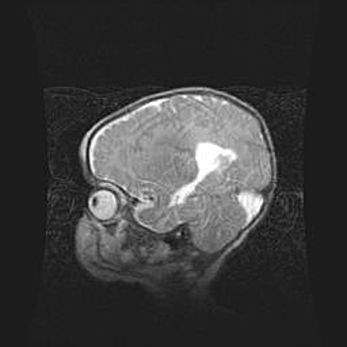

Мальформация Денди-Уокера. Киста задней черепной ямки.

Агенезия мозолистого тела.

Возраст: 2,5 месяца

Вес: 2420 г

Пол: женский

Окружность головы: 37 см

Срок гестации: 32 недели

Мальформация Денди—Уокера — редкий вид патологии ЦНС, представляющий собой врожденный порок развития каудального отдела ствола и червя мозжечка, ведущий к неполному раскрытию срединной (Мажанди) и латеральных (Лушка) апертур IV желудочка мозга. Для этогно синдрома характерна триада симптомов: гипотрофия червя мозжечка и/или полушарий мозжечка, кисты задней черепной ямки, гидроцефалия различной степени. В 70% случаев порок сочетается и с другими аномалиями головного мозга, в частности с агенезией мозолистого тела.